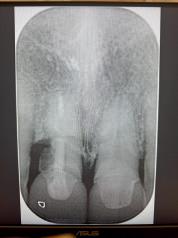

Case 1: Anterior tooth restoration with composite

Case 2: Posterior tooth restoration with composite

Restorations with BEAUTIFIL II LS, BEAUTIFIL Flow Plus X and OneGloss by Erik-Jan Muts, M.Sc., Netherlands